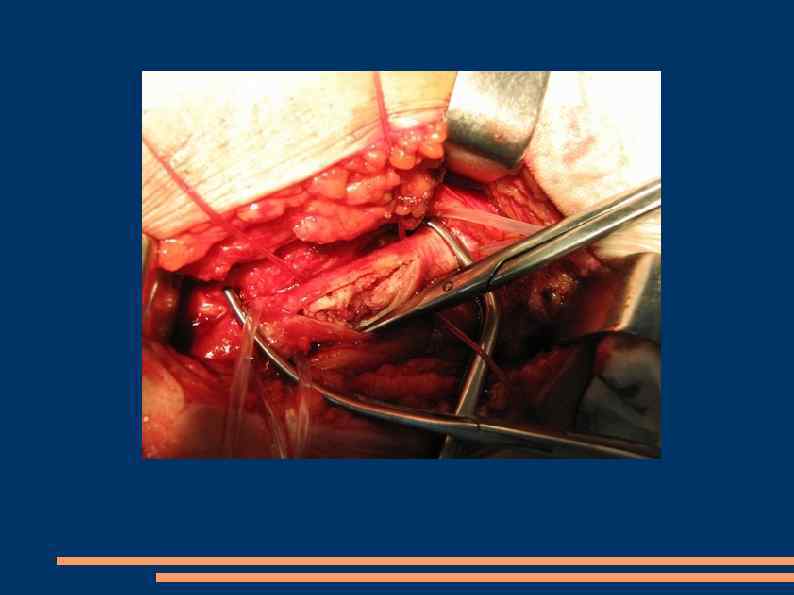

Эндартерэктомия Полуоткрытый способ Закрытый Открытый эверсионный

Открытая эндартерэтомия

Полузакрытая эндартерэктомия

Эверсионная эндартерэктомия